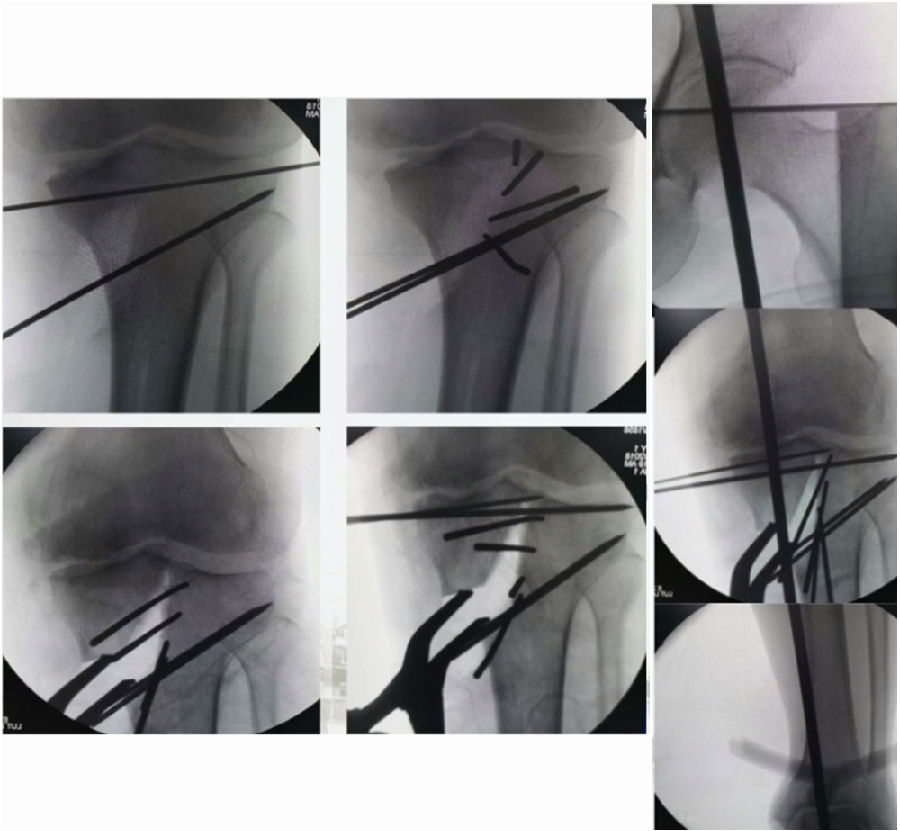

术中影像

结合影像学来看,该患者单纯用闭合截骨或开放截骨,对肢体均有影响,所以决定采用混合型截骨。术中混合截骨旋转中心选在内外1/3处,先做闭合楔,然后顺势将开放楔敲开,达到术前设计的目标力线。术后随访力线达到要求。

术后X线